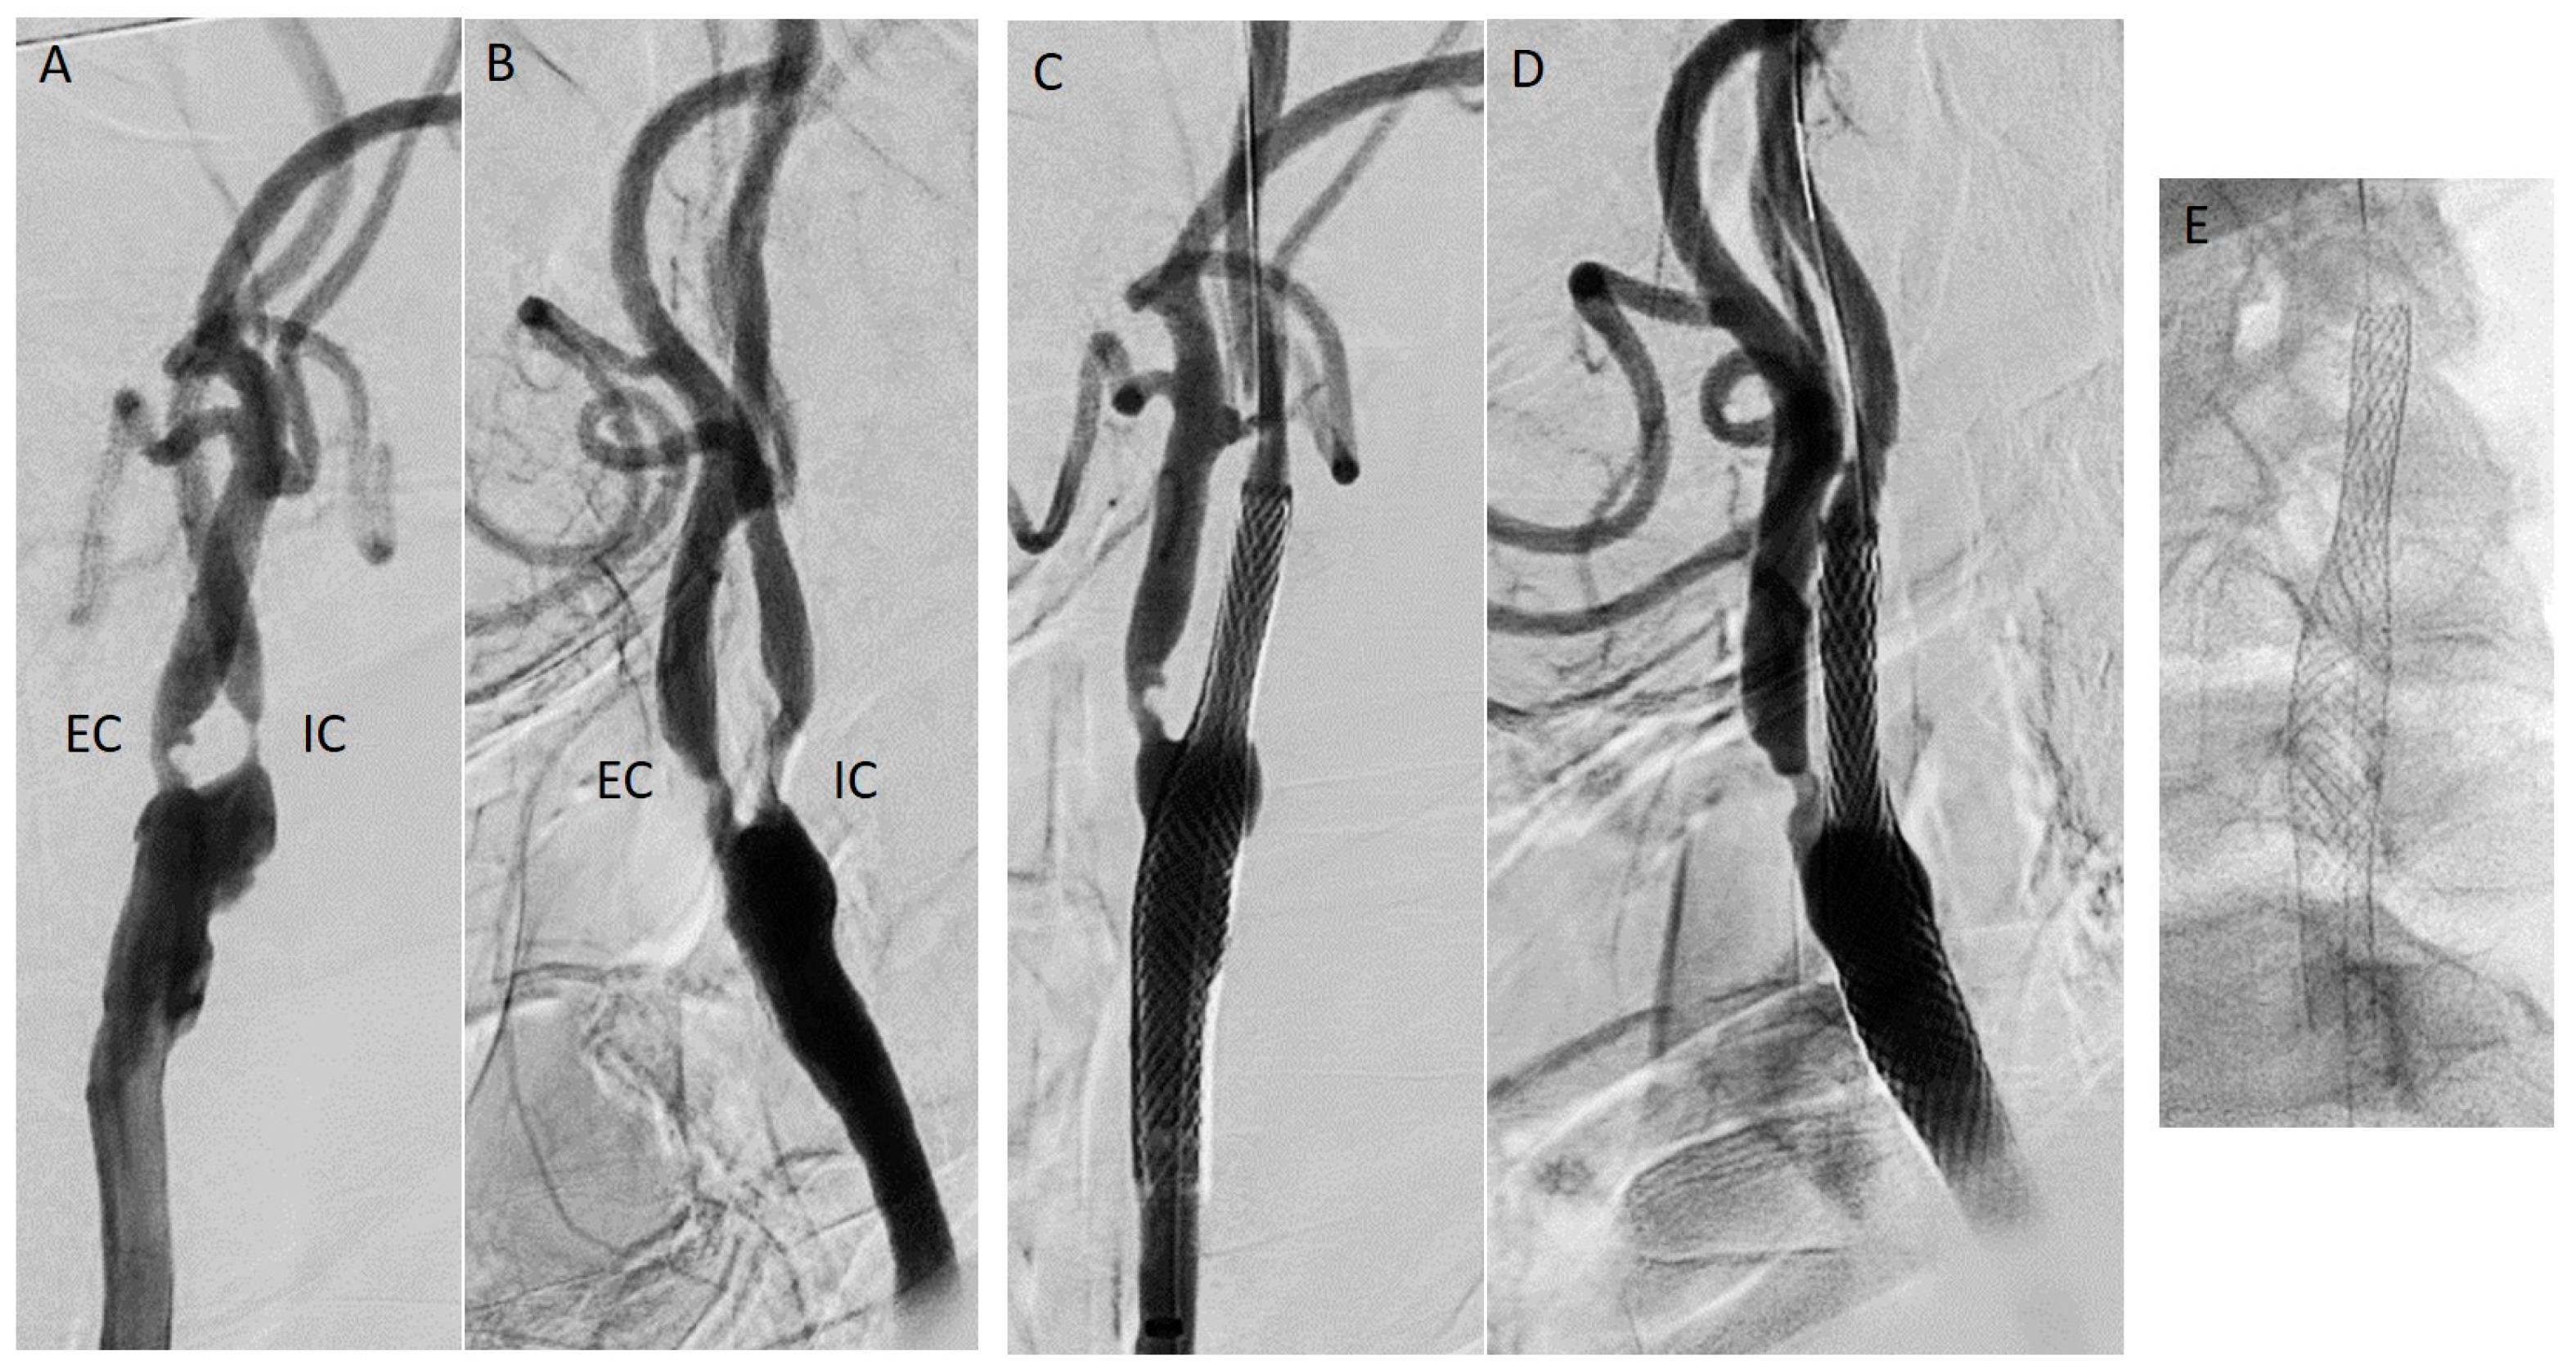

8.1.1. Carotid Artery Stenting (CAS)